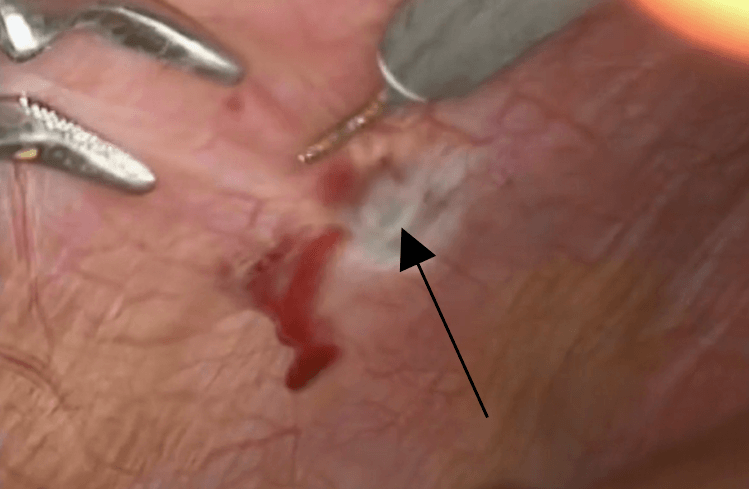

Endometriose no diafragma, assinalado na seta preta. Imagem de videolaparoscopia.